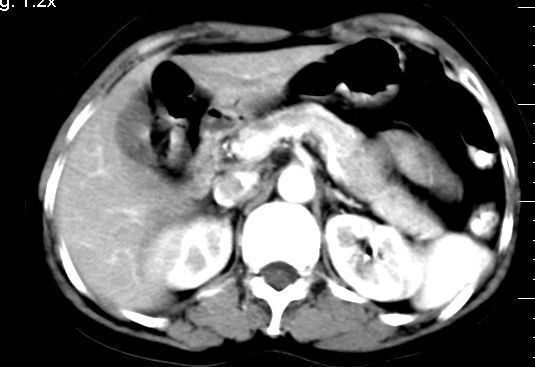

标题: CT10752:F,52岁,反复上腹部疼痛,平扫+增强. [打印本页]

f、52岁,反复上腹部疼痛2年。肺结核病史10多年,胸片双上肺结核纤维化。

ct表现:

肝大小形态未见异常,肝内外胆管无扩张,肝s8段见一动脉期明显血管样强化结节,门脉期呈高密度,延迟期呈等密度,胆囊不大,增强扫描见胆囊及胆囊颈管壁增厚,有强化。

双肾灌注良好,代谢增快,动脉期肾盂见造影剂,左肾下极背侧见一略低密度病灶,延迟期见似不强化囊肿,双侧肾上腺未见异常。

胰腺及脾未见异常。肾门水平腹膜后见小淋巴结。腹腔未见积液征象。

诊断:

1、胆囊炎(轻度)。

2、肝s8段结节,考虑小血管瘤。

3、左肾下极低密度灶,考虑囊肿可能性大,建议随访,除外小肾癌(无强化可以基本除外)。

4、目前ct表现尚不能解释患者上腹部疼痛,建议上消造影检查,除外胃炎等疾患。